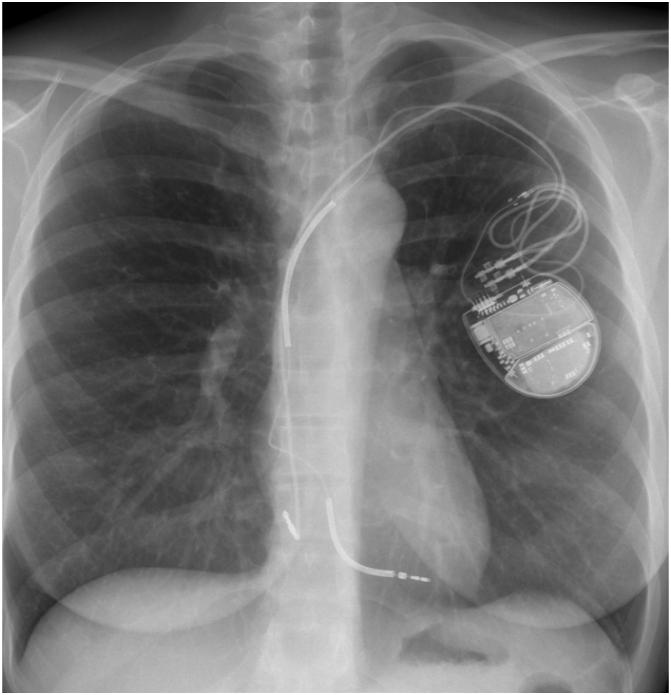

Recurrent implantable cardioverter-defibrillator shocks due to automatic deactivation of a right ventricular lead noise discrimination algorithm.

https://cdn.ncbi.nlm.nih.gov/pmc/blobs/6e69/9596365/598317e4b453/gr1.jpg